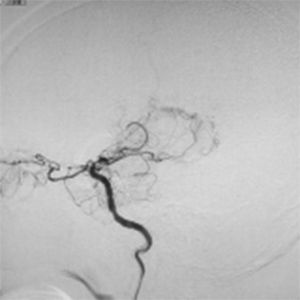

閉塞した脳血管

バイパス術で増加した脳血管

バイパス術により脳血流が正常化